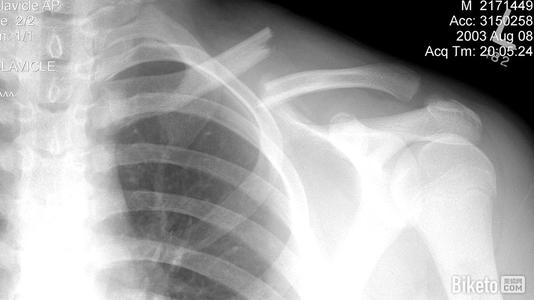

本病的辅助检查方法主要是影像学检查,锁骨骨折常发生在中段。多为横断或斜行骨折,内侧断端因受胸锁乳突肌的牵拉常向上后移位,外侧端受上肢的重力作用向内、下移位,形成凸面向上的成角、错位缩短畸形。

1.X线检查

疑有锁骨骨折时需摄X线像确定诊断。一般中1/3锁骨骨折拍摄前后位及向头倾斜45°斜位像。拍摄范围应包括锁骨全长,肱骨上1/3、肩胛带及上肺野,必要时需另拍摄胸片。前后位像可显示锁骨骨折的上下移位,45°斜位像可观察骨折的前后移位。

内侧断端因受胸锁乳突肌的牵拉常向上后移位,外侧端受上肢的重力作用向内、下移位,形成凸面向上的成角

外1/3锁骨骨折中,一般可由前后位及向头倾斜40°位X线像做出诊断。锁骨外端关节面骨折,常规X线像有时难以做出诊断,常需摄断层X线像或行CT检查。

锁骨骨折内固定术后